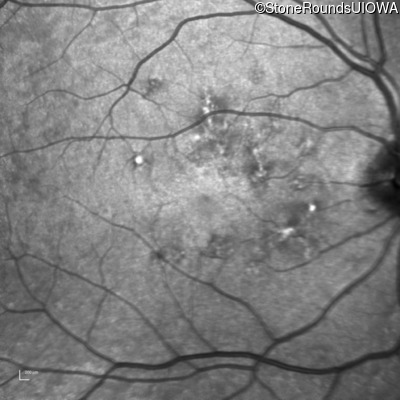

Infrared Fundus Photograph - Right - 20/20 -1

Exemplar